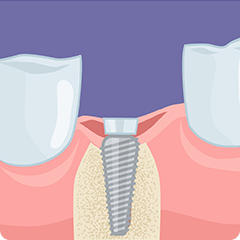

セラミックなどで作製した人工歯を、インプラントの上に装着します。天然歯のような見た目と機能を担います。

アバットメント

上部構造とインプラントを連結する部品です。人工歯を支える支台の役割を果たします。

インプラント

歯槽骨に埋め込むチタン製の人工歯根です。骨との結合(オッセオインテグレーション)を促進する構造を持ち、インプラントの土台となります。